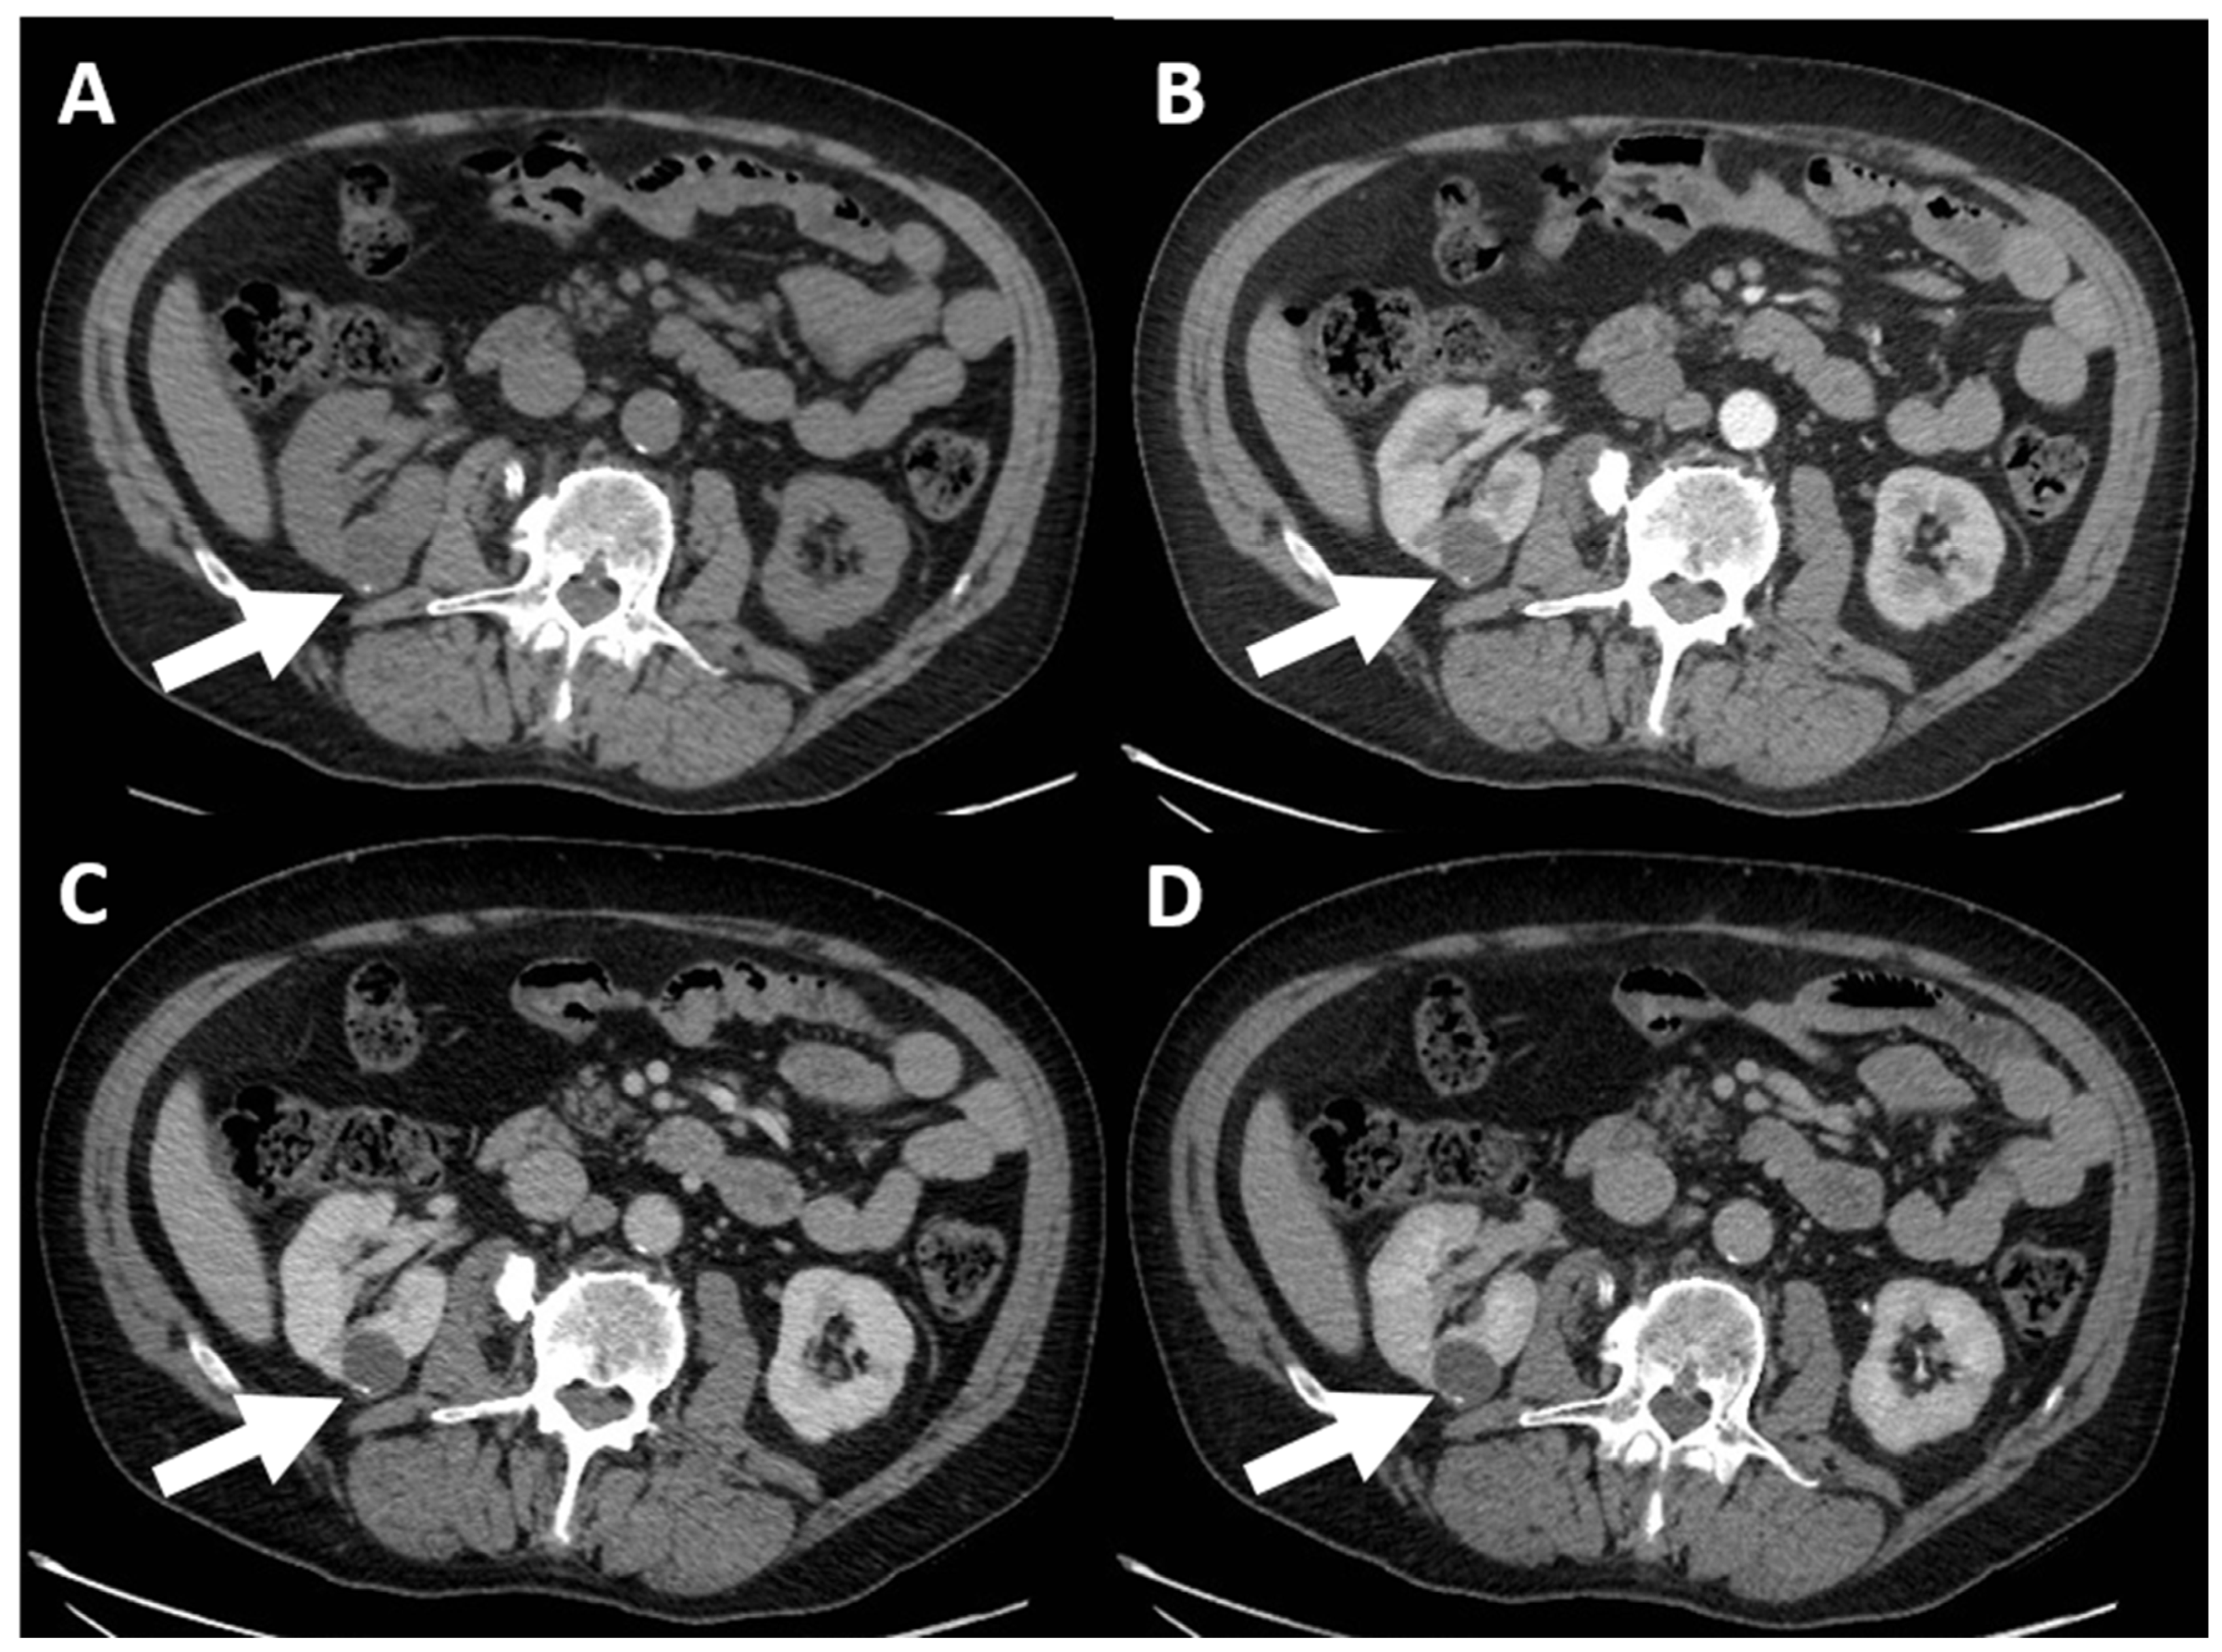

4. Computed Tomography Assessment

4.1. Lesion Density

4.3. Enhancement

- (d) Class III: indeterminate cystic mass, which includes cystic masses characterized by one or more thickened (≥4 mm) or enhancing and irregular (≤3 mm and with convex marginal protrusions) walls or septa [91]. Bosniak III masses (Figure 4) are “potentially” malignant in that they have an intermediate probability of malignancy (about 55%) [97]. Therefore, urologic consultation should be considered for possible partial nephrectomy or radiofrequency ablation in candidates unfit for surgery [99].

- (e) Class IV: clearly malignant cystic mass, which includes masses characterized by the presence of one or more enhancing nodules (≥4 mm convex protrusion with obtuse margins, or a convex protrusion of any size that has acute margins). A Bosniak IV mass (Figure 5) has a malignancy rate of about 90% and therefore requires urologic consultation to perform partial or total nephrectomy [100].